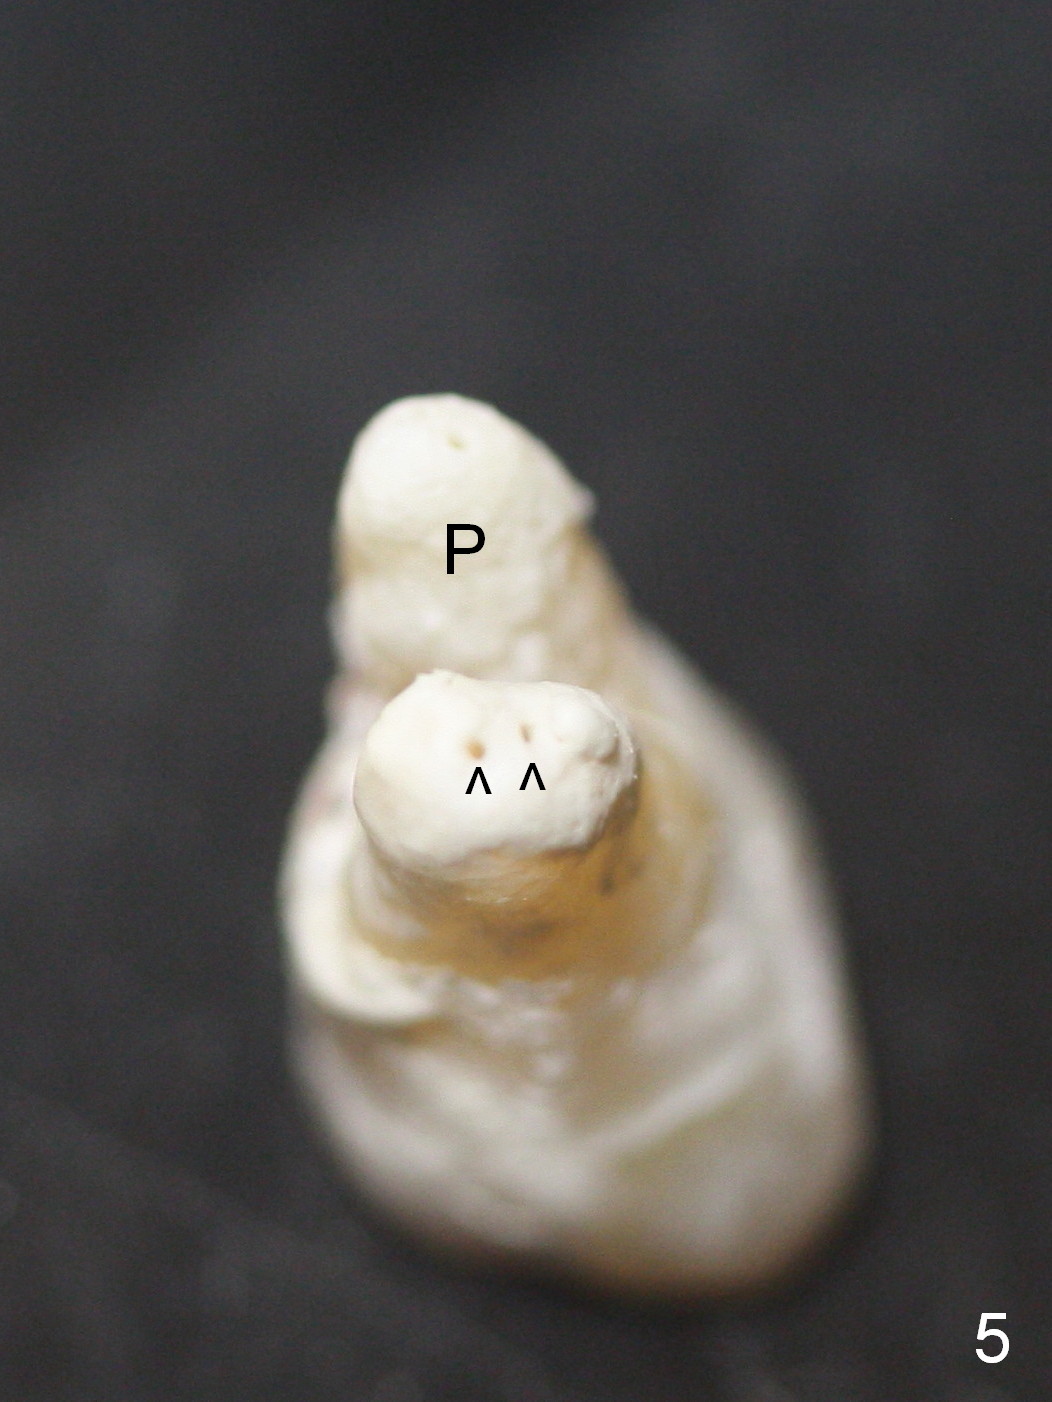

The furcation of the upper 2nd molars is variable. For example, the buccal roots of the 2nd molar may be fused (Fig.4-6). The septum may be destroyed due to infection such as in this case (Fig.4). An immediate implant could be placed in the septum or the buccal and palatal sockets, depending upon the integrity of the buccal and palatal plates.